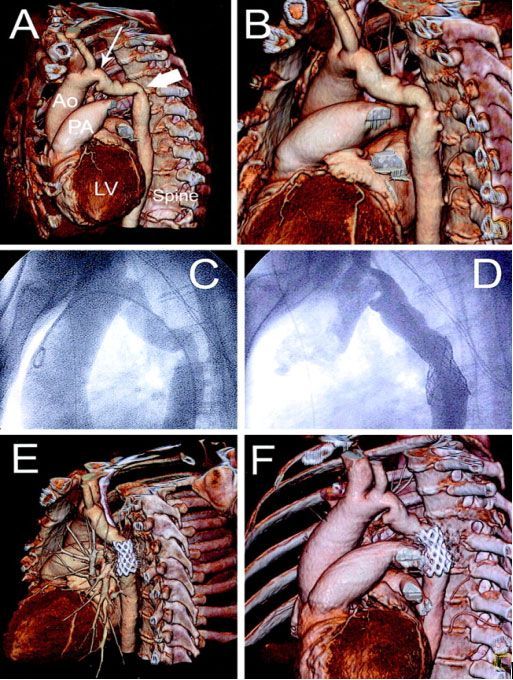

4. состояния после перенесенных после операций аорто - коронарного шунтирования (АКШ) или чрезкожной транслюминальной ангиопластики коронарных артерий (ЧТКА) с имплантацией стентов для определения состоятельности аорто - коронарных шунтов или внутрисосудистых эндопротезов [7,8] (рис.№ 4).

![]() |

| Рис.4. 3-D реконструкция у пациента после АКШ и ЧТКА со стентированием. Рисунок слева: стрелками отмечены аорто - коронарные шунты. Рисунок справа: стеноз проксимального сегмента коронарной артерии и ниже - функционирующий стент.

|

| Рис.5. КАГ (E, F) и МСКТ коронарных артерий( A, B, C, D). Гемодинамически значимый стеноз ПКА (стрелки). |